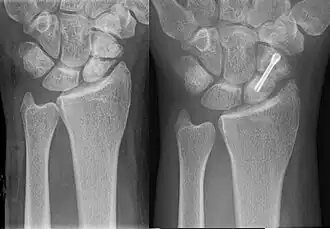

![]() | |

| An X-ray showing a fracture through the waist of the scaphoid | |

-

A subtle scaphoid fracture -

A more obvious scaphoid fracture on a scaphoid view X ray -

Radiolucency around a 12 days old scaphoid fracture that was initially barely visible.[13]